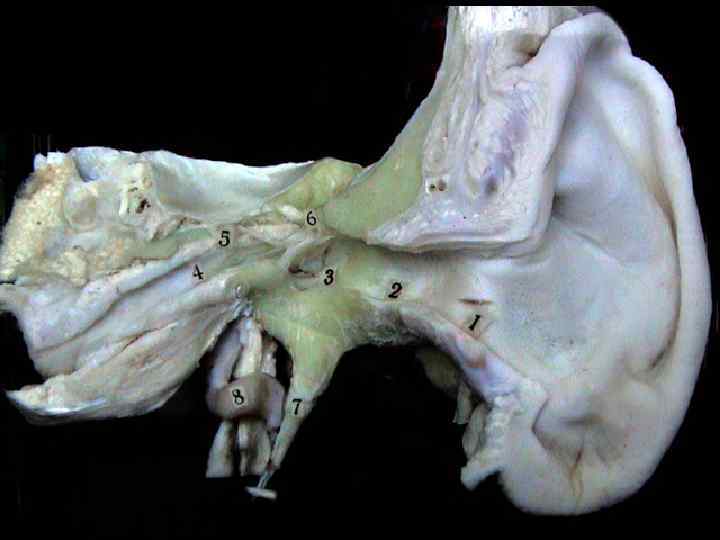

Подсистема проведения информации: наружное ухо: раковина, наружный слуховой проход среднее ухо: слуховая труба, кинематические узлы и мембраны, перилимфа, эндолимфа, кортиколимфа

Схема аппарата звукопроведения meatus acusticus externus ossicula auditus membrana tympanica secundaria (foramen rotundum) malleus, incus, stapes fenestra vestibuli helicoterma scala tympani scala vestibuli

Tuba auditiva (otosalpinx) Состоит из хрящевой (эластической) части - внутренняя, и костной - наружная Обе части образуют угол 150° Общая длина 37 мм Диаметр в барабанной полости до 6 мм Сужение - в участке перехода хрящевой части в костную (1, 5 мм)

Кровоснабжение и иннервация слизистой барабанной полости • A – a. tympanica anrerior (a. maxillaris) • B – rami caroticotympanici (aa. plexus carotis internus) • a. tympanica superioir (a. meningea media). • a. tympanica posterior (a. stylomastoidea) • a. tympanica inferior (a. pharyngea ascendens) • C – n. tympanicus (ganglion inferior IX), • D – n. facialis (VII) (n. stapedius, chorda tympani) • r. auricularis (X) • E – a. carotis interna (nn. caroticotympanici )